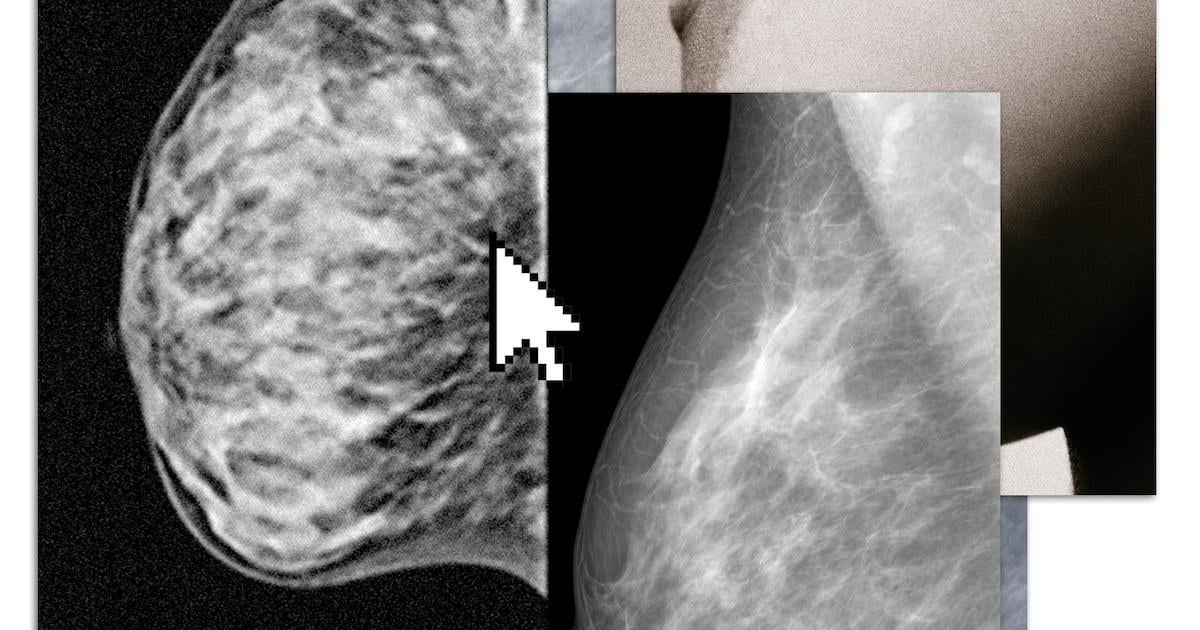

Sie sind schwarz mit hier und da ein paar weißen Wolkenstreifen und die Frage ist: Was sehe ich? Mit nur wenigen Mausklicks erscheinen die Brustfotos, die ich kürzlich im Mammo-Bus gemacht habe, auf meinem Computerbildschirm. Ich habe sie bei der Niederländischen Bevölkerungsumfrage angefordert und nach einem Monat eine sichere E-Mail mit einer Erklärung zum Herunterladen der Bilder erhalten. „Die Informationen können nur von speziell geschultem medizinischem Personal interpretiert werden“, hieß es. Jetzt schaue ich und ich zweifle.

Ich möchte die Röntgenaufnahmen sehen, um herauszufinden, wie hoch meine Brustdichte ist. Brüste bestehen aus Fett, Bindegewebe und Drüsengewebe und wer über dichtes Brustgewebe, also viel Binde- und Drüsengewebe, verfügt, hat nicht nur ein doppelt so hohes Risiko, an Brustkrebs zu erkranken, sondern hat auch das Pech, dass ein Tumor im Mammogramm seltener sichtbar ist. Drüsengewebe ist weiß, ebenso wie ein Tumor. Es gibt vier Kategorien der Brustdichte, die von A bis D ansteigen. Für Frauen mit D (etwa 80.000 pro Jahr) bietet eine zusätzliche MRT einen Mehrwert. Im MRT ist ein Tumor oft sichtbar. Umfangreiche und einzigartige niederländische Forschung, vor sechs Jahren in der besten medizinischen Fachzeitschrift der Welt veröffentlichtzeigt, dass bei dieser Gruppe von Frauen mit einem MRT jedes Jahr Hunderte zusätzlicher Tumoren entdeckt werden können. Das erspart ernsthafte Behandlungen und kann Leben retten.

Wenn ich anhand der Fotos herausfinden kann, wie hoch meine Brustdichte ist, kann ich möglicherweise auf eigene Kosten ein MRT in einer Privatklinik durchführen lassen. Aber deuten diese weißen Streifen auf meinen Fotos auf die Dichte B oder vielleicht C hin? Bedeutet die Tatsache, dass ich auf den Bildern auch Schwarz sehe, dass ich kein D habe?

„Sie sehen auf Ihrem Bildschirm das gleiche Bild wie ich jeden Tag“, sagt Ritse Mann, Brustkrebsradiologe am Antoni van Leeuwenhoek. „Wenn das Bild weitgehend schwarz ist, liegt kein dichtes Brustgewebe vor.“ Wenn es größtenteils weiß ist, wird die Interpretation für einen Laien deutlich schwieriger: Ist es C oder D? Dass die Frauen selbst mit diesen Bildern hausieren gehen müssen und ihnen gegenüber unruhig werden, sei natürlich nicht die Absicht, sagt er.